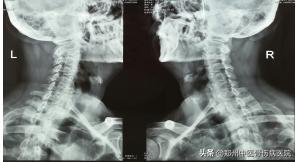

颈部生理曲度变直,活动稍受限,颈、肩部肌肉稍紧张,其中双侧颈肩部至三角肌处痛点明显。左侧椎间孔挤压试验(+)

辅助检查:颈椎MRI:C3/4--C5/6椎间盘退行性病变